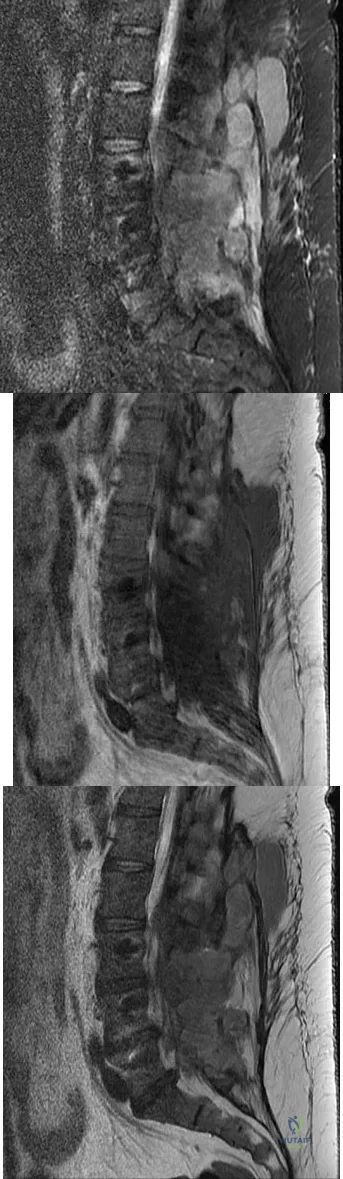

A 73-year-old woman reports a 4-month history of severe left-sided posterior buttock pain and left leg pain. The leg pain radiates into the left lateral thigh and posterior calf with cramping. Examination reveals mild difficulty with a single-leg toe raise on the left side and a diminished ankle reflex. There is also a significant straight leg raise test at 45 degrees which exacerbates symptoms. An MRI scan is shown in Figure 4. What is the most appropriate treatment at this time?

Detailed Explanation

Figures 20a through 20d show the radiographs and MRI scans of a 59-year-old woman who has had symptoms consistent with progressive neurogenic claudication and back pain for the past 9 months. In the last 6 months, nonsurgical management consisting of nonsteroidal anti-inflammatory drugs, physical therapy, and a series of epidural steroid injections have been used; however the injections, while beneficial, have provided only temporary relief of her symptoms. What is the most appropriate management at this time?

Explanation